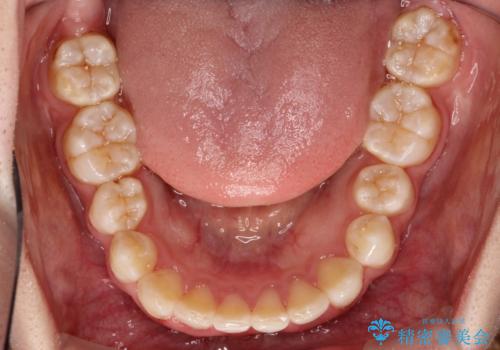

重度のガタガタのインビザラインによる非抜歯矯正

ガタガタの度合いが大きかったので少し時間がかかりましたが、非常に協力的な患者様でしたので、抜歯をせず計画通りに治療を終えることができました。